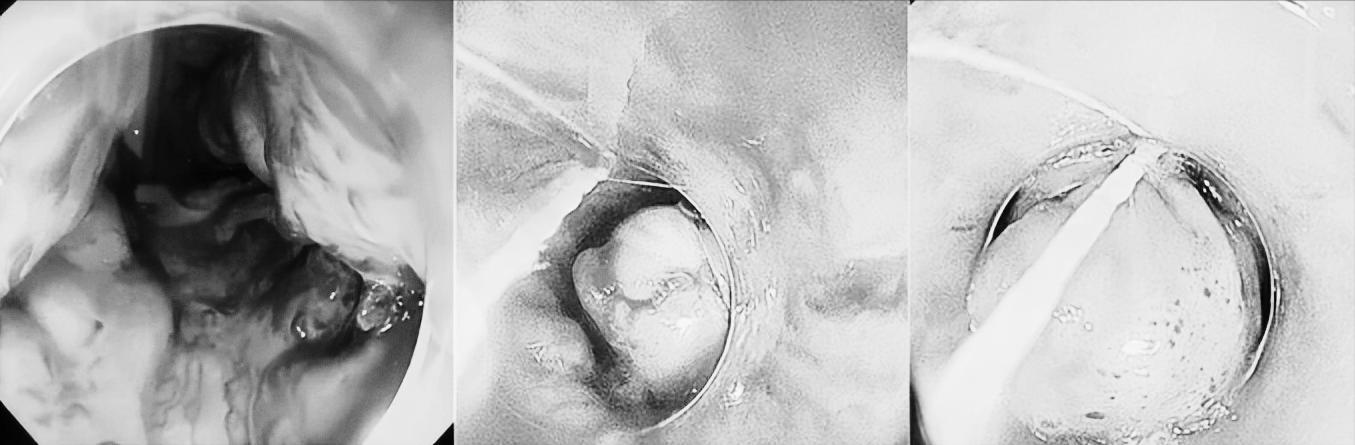

患者病情危急、出血量大,随时可能出现休克风险,救治刻不容缓。在ICU严密监护下,内镜团队沉着应战、精准操作,凭借丰富经验与娴熟配合,迅速找到食管出血部位并成功实施食管静脉曲张套扎止血,有效控制凶险病情,为后续治疗赢得关键时机。